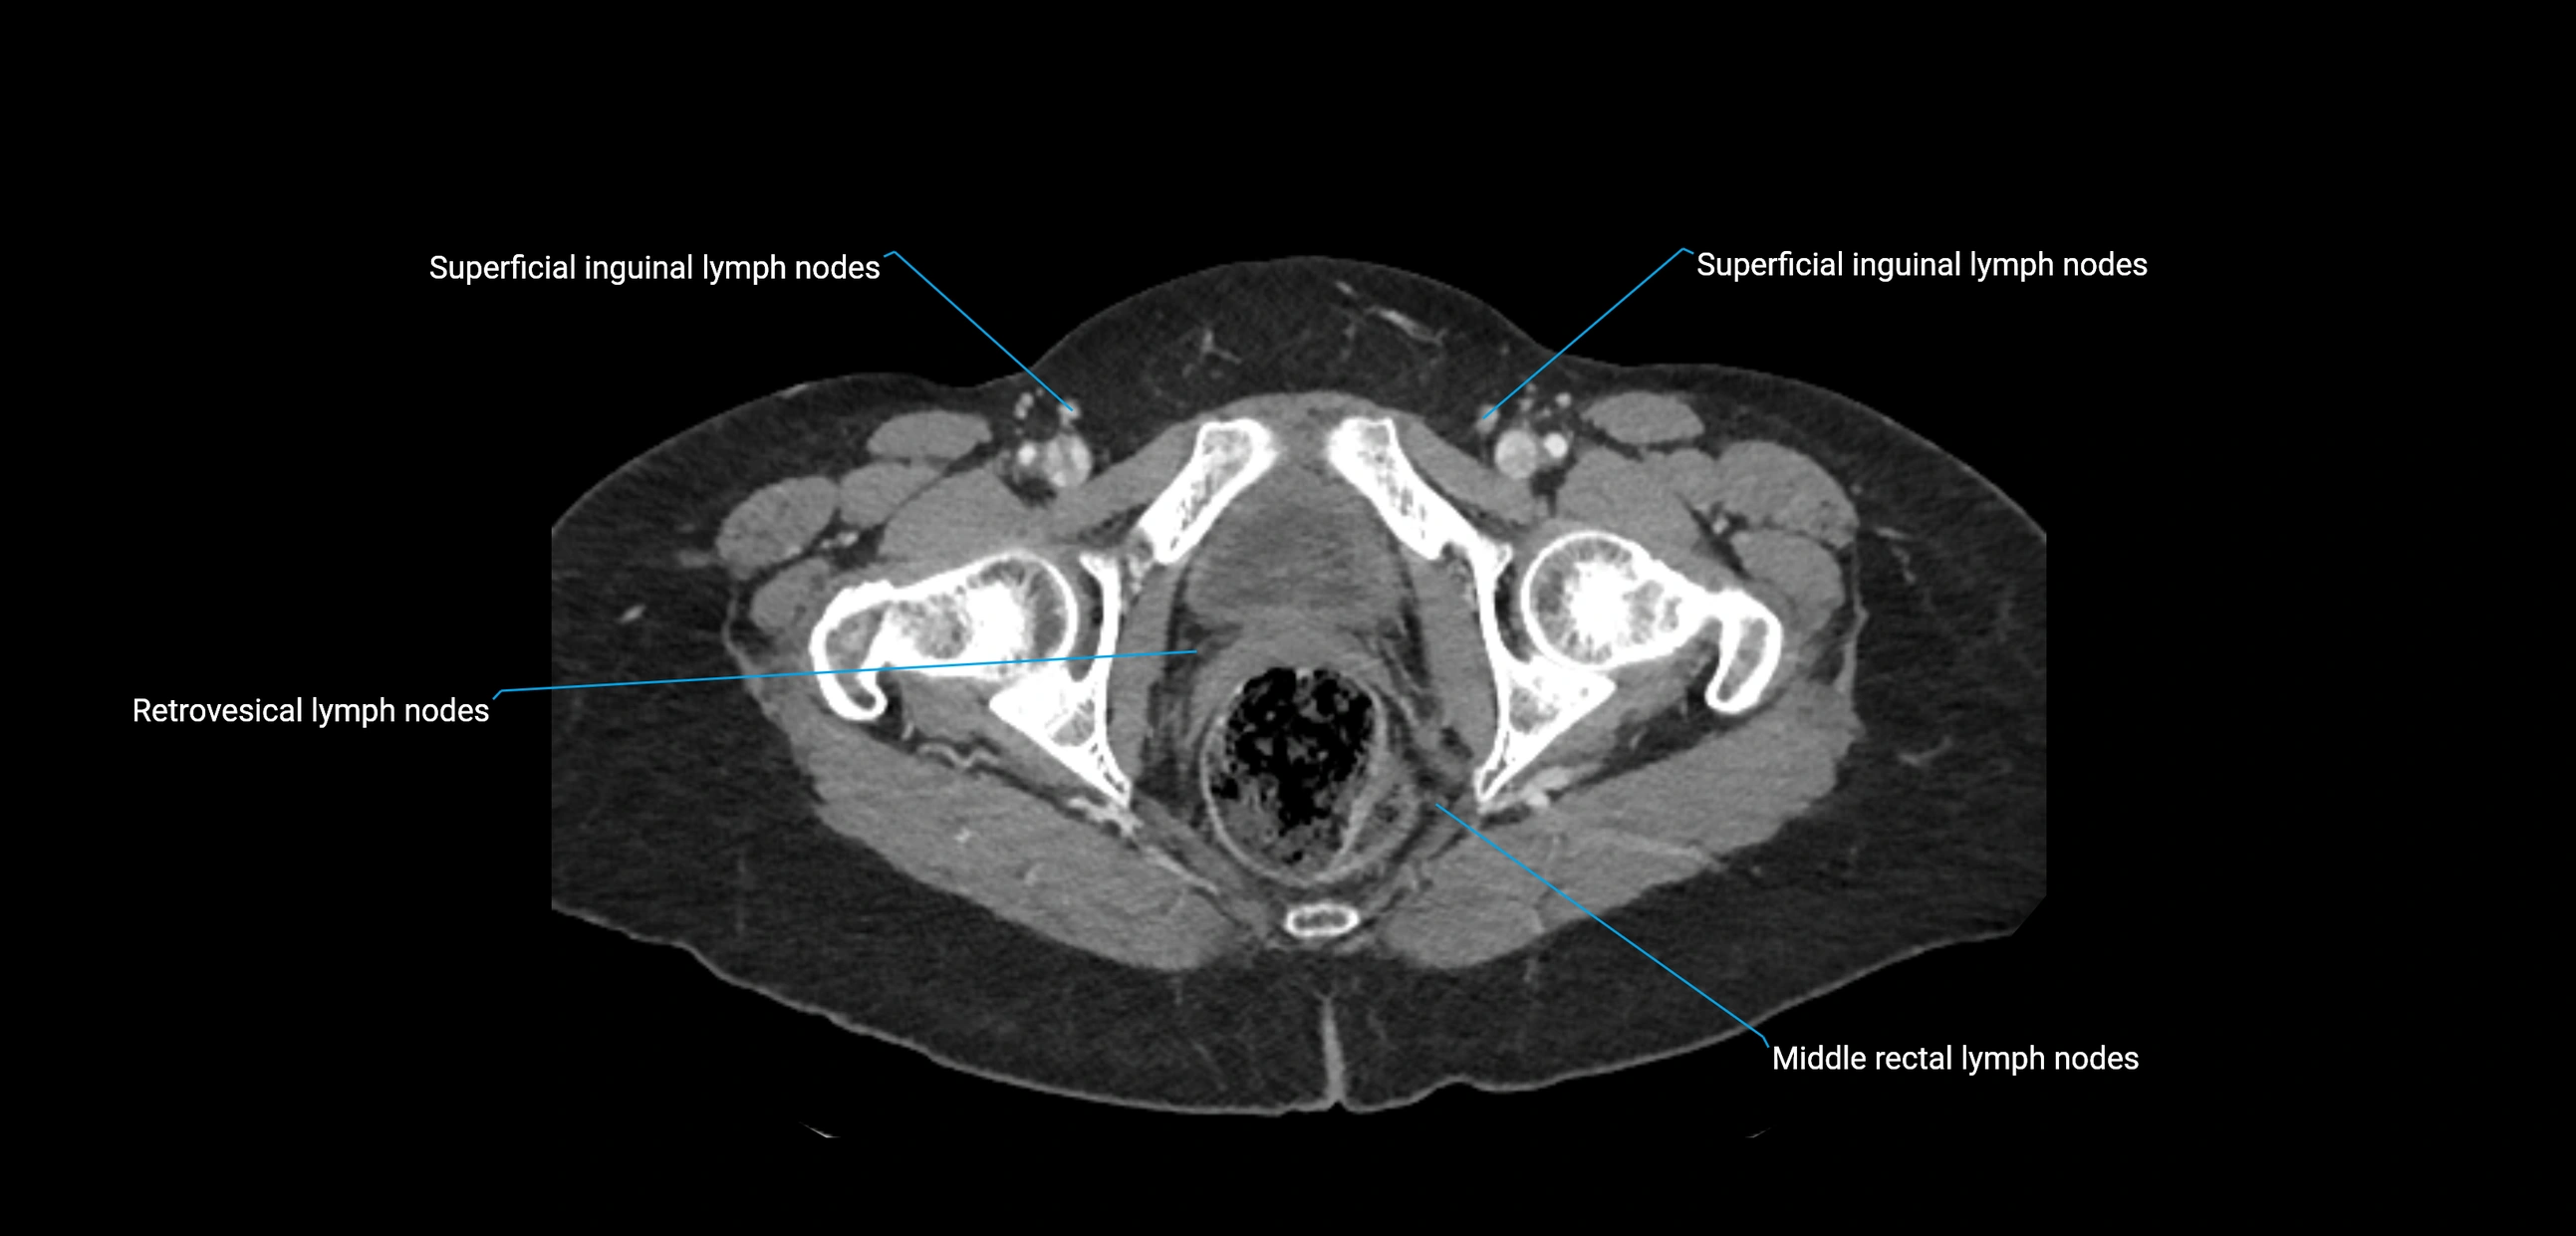

The lateral aortic lymph nodes (also called para-aortic lymph nodes) are a major group of retroperitoneal lymph nodes located along the abdominal aorta and its branches. They lie between the diaphragmatic crura superiorly and the bifurcation of the aorta at L4 inferiorly.

These nodes receive lymph from a wide range of abdominal and pelvic structures. Specifically, they drain lymph from the kidneys, suprarenal glands, gonads (testes/ovaries), uterus, uterine tubes, and pelvic organs, before converging into the lumbar lymphatic trunks, which terminate in the cisterna chyli → thoracic duct.

Clinically, the lateral aortic lymph nodes are critically important in oncology, being involved in the spread of testicular cancer, ovarian cancer, endometrial cancer, cervical cancer, renal malignancies, and retroperitoneal lymphomas. They are also key targets in retroperitoneal lymph node dissection (RPLND) for testicular tumors.

CT Appearance

CT Post-Contrast:

• Normal nodes enhance homogeneously

• Malignant nodes may show heterogeneous enhancement, central necrosis, or conglomerate formation

• Size >1 cm short axis is suspicious, though morphology and distribution are equally important